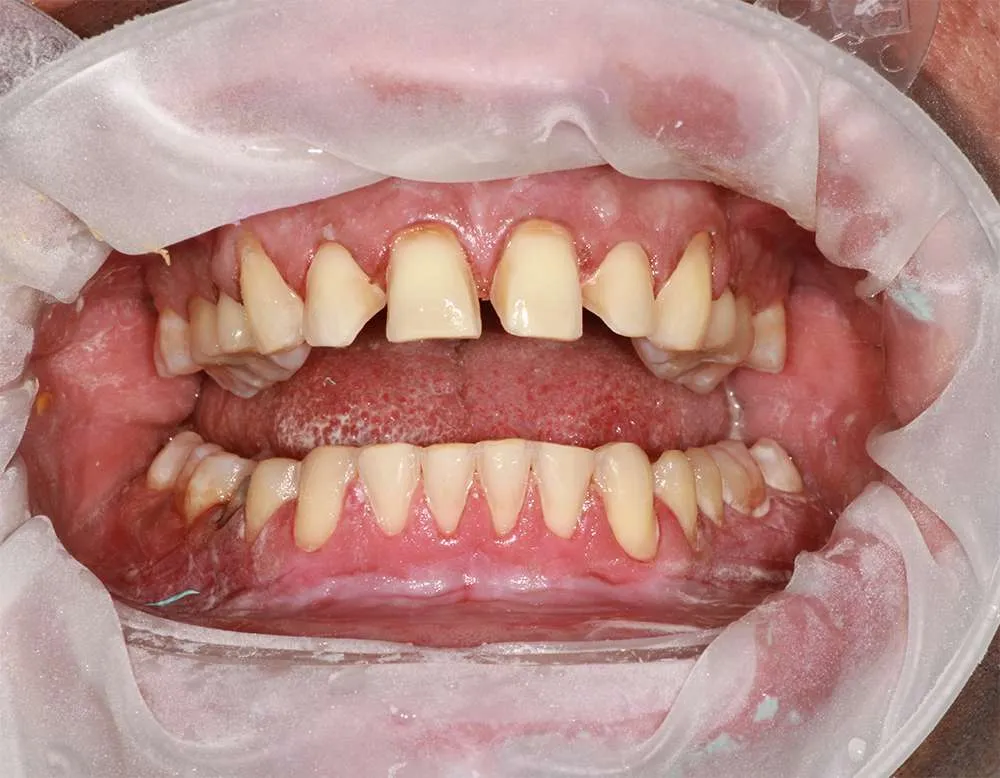

Real Stories, Real Results: Case Studies Showcasing How Our Personalized Approach Transforms Smiles and Lives

Witness the Remarkable Changes We Can Achieve

While ultra-thin veneers are a fantastic option for many patients looking to enhance their smile, they may not be suitable for everyone. Ideal candidates are those with healthy teeth and gums who are looking to correct cosmetic issues like discoloration, misalignment/crooked or small gaps. During your consultation, Dr. O'Malley will assess your dental health and determine if ultra-thin veneers are the right choice for you.